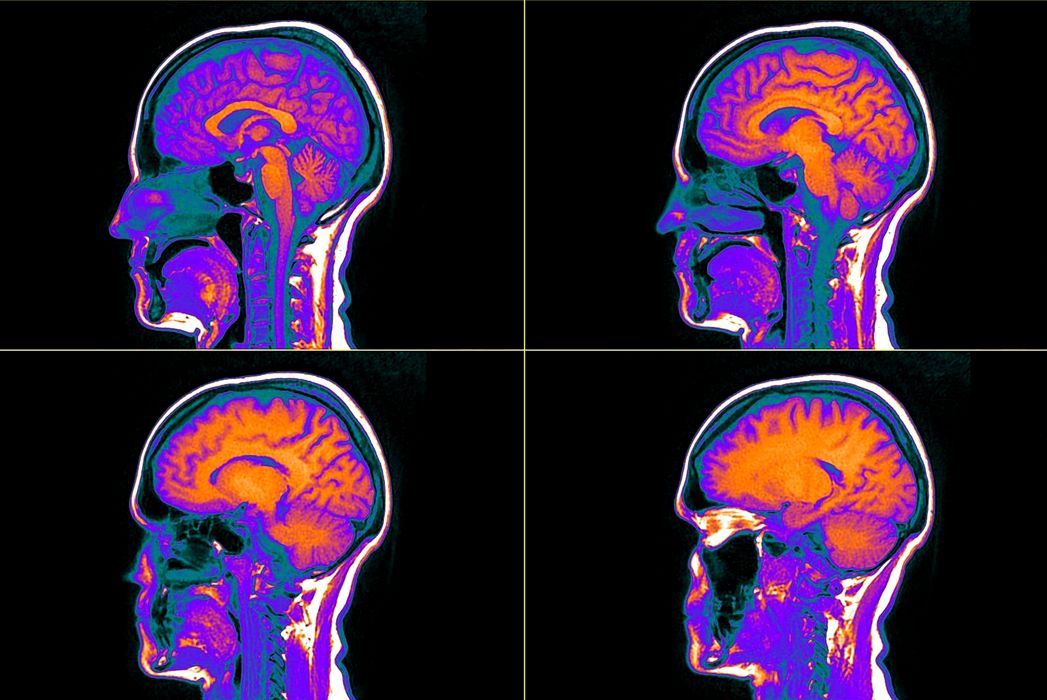

Ce au descoperit cercetătorii atunci când au scanat creierul oamenilor cu ideologii autoritariste?

Persoanele care susțin ideologii autoritariste, indiferent de orientarea politică, prezintă, potrivit unui nou studiu, particularități cerebrale neobișnuite. Ce au descoperit cercetătorii când au scanat creierii autoritariștilor? Ce au văzut cercetătorii când au scanat creierii autoritariștilor? […]